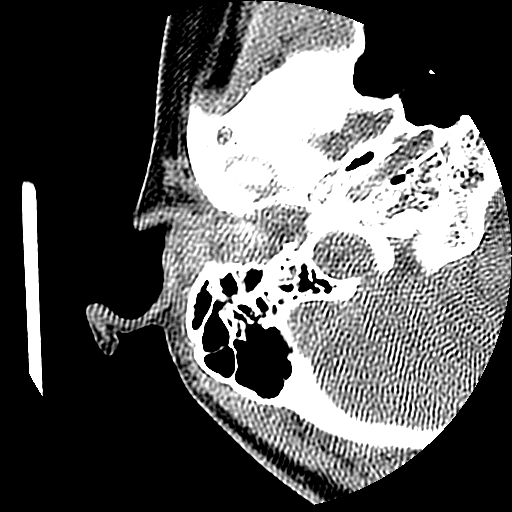

以下是引用随光逐影在2009-8-19 7:25:00的发言:[br]右侧慢性中耳乳突炎,右侧中耳腔及外耳道肉芽肿或胆脂瘤形成。